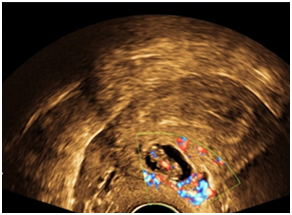

A 29-year-old multiparous woman at 11weeks’ gestation was referred to our hospital for termination of pregnancy due to suspected placenta accreta or cesarean scar ectopic by abnormal vasculature around lower uterine segment gestational sac on ultrasound. She had delivered 2male children by cesarean section. The patient underwent ultrasound due to complain of vaginal bleeding. It revealed lower uterine segment pregnancy with abnormal vasculature in the placenta bed suspicious of placenta accreta or cesarean scar ectopic pregnancy about 10weeks gestation (Figure 1). The decision was done to evacuate the pregnancy vaginally by surgical means. The patient underwent surgical evacuation under ultrasound guidance but severe vaginal bleeding occurred. The procedure was ended and uterovaginal packing was done for 24hrs. The patient was vitally stable. The procedure was performed transabdominal ultrasound examination after 24hrs that revealed bulky uterus with hematoma inside cavity and there was a defect (3cm×2.0cm) in the lower anterior uterine wall with no fluid collection in the abdomen (Figures 2-5). The patient was vitally stable with no vaginal bleeding. We removed the vaginal pack intraoperative under general anesthesia, prepared for laparotomy in case of severe bleeding. No bleeding occurred, the patient discharged after 1 week and follow-up after one month revealed normal uterus.

Figure 1 lower uterine segment with abnormal vasculature in placenta bed suspicious of early placenta accreta or cesarean scar ectopic pregnancy.